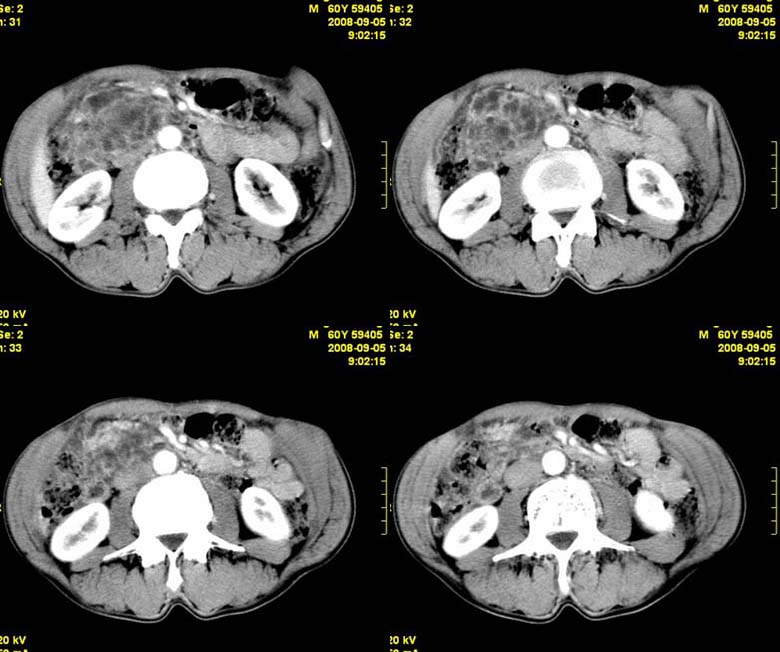

标题: CT15580:M60Y,胰腺病变,平扫+增强 [打印本页]

标题: CT15580:M60Y,胰腺病变,平扫+增强

患者,男, 60,既往有间歇腹痛病史多年,现右上腹痛,加重一月,伴右后背部疼痛,无黄疸,无发热。

胰头囊腺瘤/囊腺癌.

胰腺炎,胰液滞留性假囊肿

考虑胰腺囊腺瘤或慢性胰腺炎。

胰头区增大,胰管明显扩张,不均匀强化,且与 周围结构不清,后背疼痛,考虑为胰腺头部胰腺癌。

胰头囊腺癌

考虑胰腺囊腺瘤或慢性胰腺炎可能性大

粘液性囊腺瘤

同意胰头部囊腺癌

胰头囊样增大不均匀强化,腺管扩张。结合病史首诊慢性胰腺炎、假性囊肿